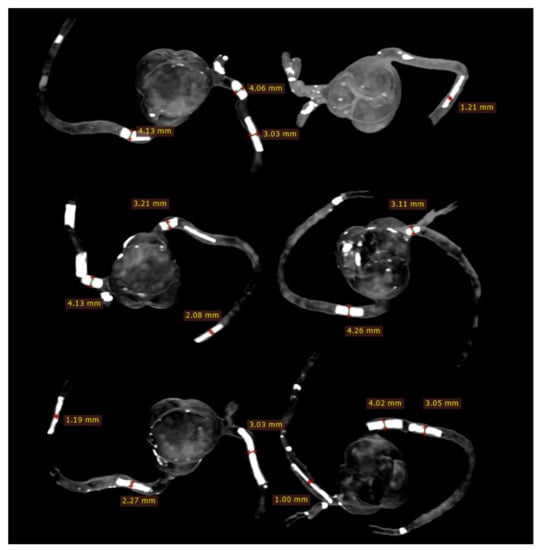

2.4. 2D and 3D Image Reconstruction and Assessment

CCTA images in DICOM format were transferred to a separate workstation for image processing and analysis using RadiAnt DICOM viewer 2020.1.1 (Medixant, Poznan, Poland). Two-dimensional axial images were reconstructed into MIP and 3D volume rendering (VR) views for visualisation of calcified plaques and measurements of plaque dimensions. For VR views, we first used a wide window width (window width and window level: 1250 and 250) to allow visualisation of plaque and coronary lumen. Then, we narrowed the window width (window width and window level: 1050 and 210) to focus on visualisation of the calcified plaques. Measurements of plaque diameter and length were performed on MIP and VR images (wide and narrow window widths), with the results compared to those from the actual sizes of these plaques and any significant differences determined. Measurements were conducted by an assessor (with more than 15 years of experience in cardiac CT imaging) and performed three times at different locations of each plaque with the mean values used as the final ones for comparisons. Figure 5 shows an example of measuring these plaques based on the MIP images, while Figure 6 displays measurements based on two VR views with the use of wide and narrow window widths. According to Society of Cardiovascular Computed Tomography (SCCT) guidelines, although multiplanar reformation is preferred to delineate the plaque morphology and coronary lumen changes, MIP images are useful for identifying artifacts, as well as the presence and position of the coronary lesions, while VR images are useful for demonstrating spatial relationships between coronary lesions and vessels []. As our purpose of this study was to focus on the blooming artifacts associated with heavy calcifications in the coronary arteries instead of assessing lumen stenosis, we compared MIP with VR visualisation tools in this experiment.

Figure 6.

Measurement of plaque dimensions on 3D volume rendering images with the use of different windowing. (A) Measurements of plaque dimensions on wide window width (window width and window level: 1250 and 250). (B) Measurement of plaque dimensions at the same plaque locations with narrow window width (window width and window level: 1050 and 210).

Figure 8 demonstrates coronal and oblique MIP images showing these calcified plaques in the coronary artery models, while Figure 9 presents VR images with window width changed. These 2D and 3D images clearly demonstrate the calcified plaques in the coronary arteries.